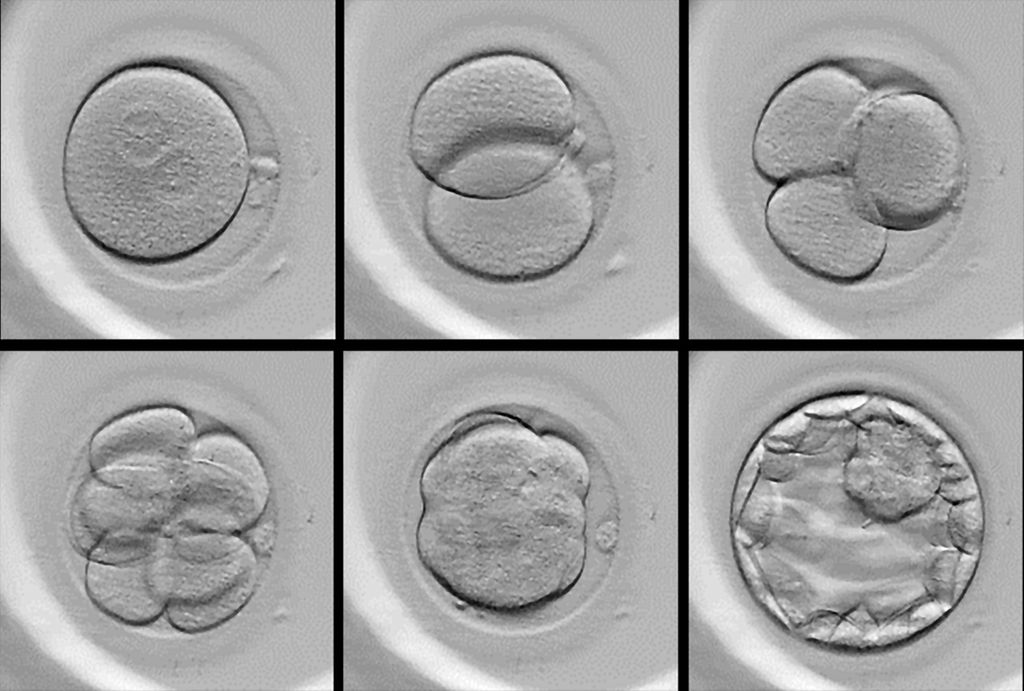

Die Kulturbedingungen wurden inzwischen so weit verbessert, dass eine Kultur der Embryonen routinemäßig bis zum fünften Tag ins sog. „Blastozystenstadium“ möglich ist. Die Beurteilung erfolgt in dieser Zeit durch erfahrene Embryolog:innen anhand von Kriterien wie Symmetrie, Anzahl der Blastomeren und Fragmentation (Abb. 1). Bisher war das eine „statische“ Beurteilung, die Embryonen konnten dazu nur kurz dem Inkubator entnommen werden, um die Kulturbedingungen möglichst wenig zu beeinflussen. Die sog. „Time lapse“-Technologie eröffnet jetzt völlig neue Möglichkeiten. Die Kombination aus Inkubator und Mikroskop liefert kontinuierliche Bilddaten über mehrere Tage, die sich zu einem dynamischen Zeitrafferfilm zusammenfassen lassen. Plötzlich steht dadurch eine Vielzahl von morphokinetischen Parametern zur Verfügung, z.B., wie viele Stunden jeder Embryo bis zur ersten Zellteilung benötigt. Die AI-Modelle wurden mit großen Mengen dieser Parameter trainiert und bieten mittlerweile eine vergleichbare, wenn nicht sogar überlegene Genauigkeit, den Embryo mit der höchsten Implantationswahrscheinlichkeit auszuwählen. Beispiele dazu sind AIVF™, Embryo Assist™ von ALIFE, Chloe™ von Fairtility, EmbryoAID™ von MIM Fertility oder Violet™ von FutureFertility.

Abb. 1: Stadien der Eizell- und Embryonalentwicklung während eines IVF-Zyklus